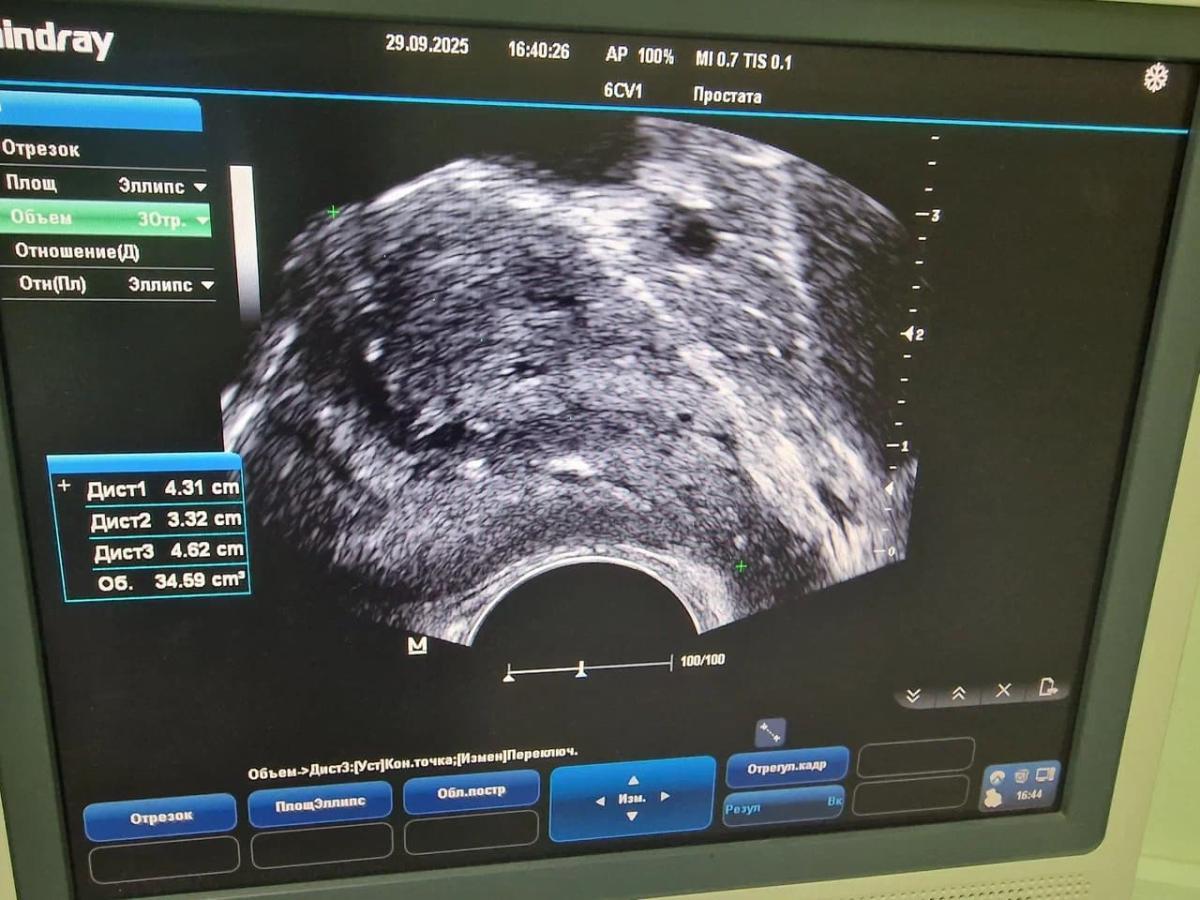

ТРУЗИ предстательной железы

Это ультразвуковое трансректальное исследование простаты, выполняемое через прямую кишку.

Исследование дает возможность детально оценить состояние тканей органа.

Определить его величину, границы, положение, выявить наличие патологических очагов, их количество, размеры и точную локализацию.

С помощью ТРУЗИ можно обнаружить опухоли в простате, гнойниковые очаги, кальцинированные конкременты.